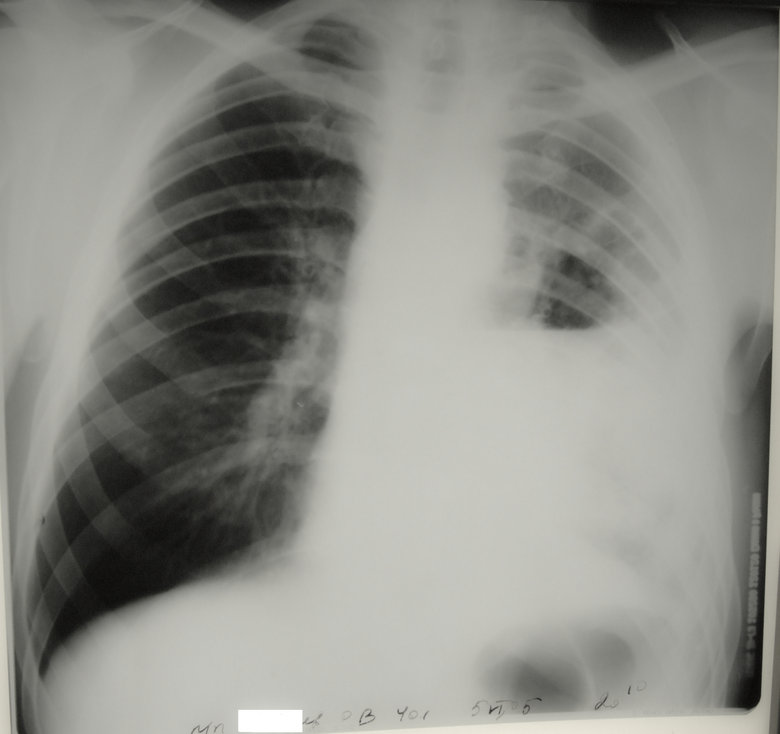

IMG_6775.jpg

IMG_6775.jpg [ 153.03 KiB | Просмотров: 14628 ]

Обсуждалось здесь https://vk.com/club84409679?w=wall-84409679_8773%2Fall